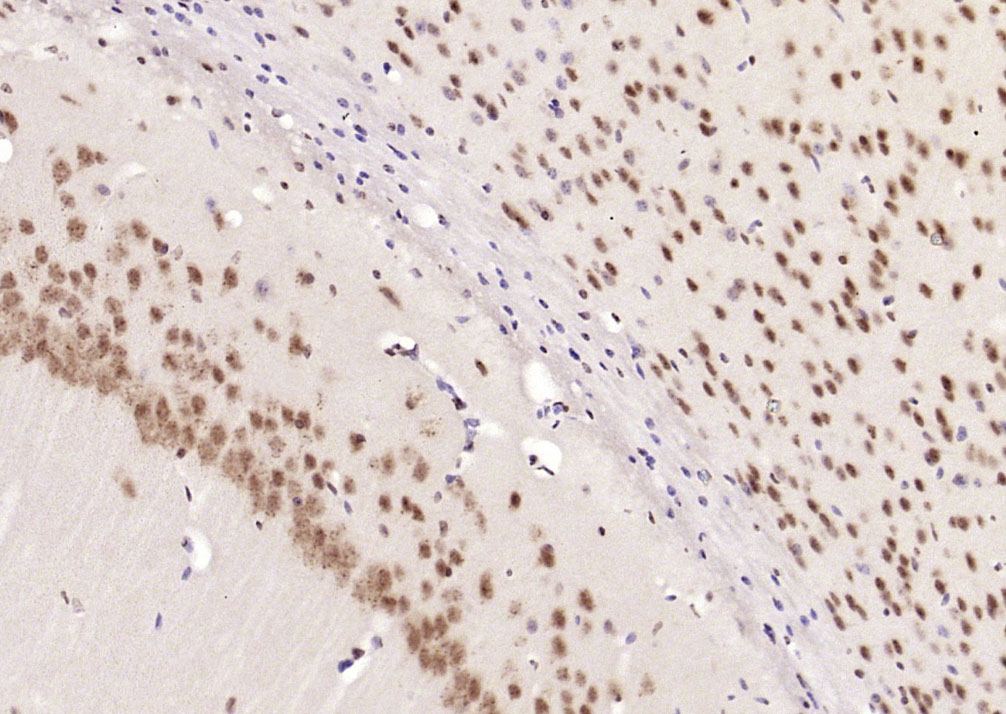

Paraformaldehyde-fixed, paraffin embedded (Mouse brain); Antigen retrieval by boiling in sodium citrate buffer (pH6.0) for 15min; Block endogenous peroxidase by 3% hydrogen peroxide for 20 minutes; Blocking buffer (normal goat serum) at 37°C for 30min; Antibody incubation with (Alpha B Crystallin) Polyclonal Antibody, Unconjugated (bs-4651R) at 1:400 overnight at 4°C, followed by operating according to SP Kit(Rabbit) (sp-0023) instructionsand DAB staining.

Paraformaldehyde-fixed, paraffin embedded (Rat brain); Antigen retrieval by microwave in sodium citrate buffer (pH6.0) ; Block endogenous peroxidase by 3% hydrogen peroxide for 30 minutes; Blocking buffer (3% BSA) at RT for 30min; Antibody incubation with (Alpha B Crystallin) Polyclonal Antibody, Unconjugated (bs-4651R) at 1:400 overnight at 4°C, followed by conjugation to the secondary antibody (labeled with HRP)and DAB staining.